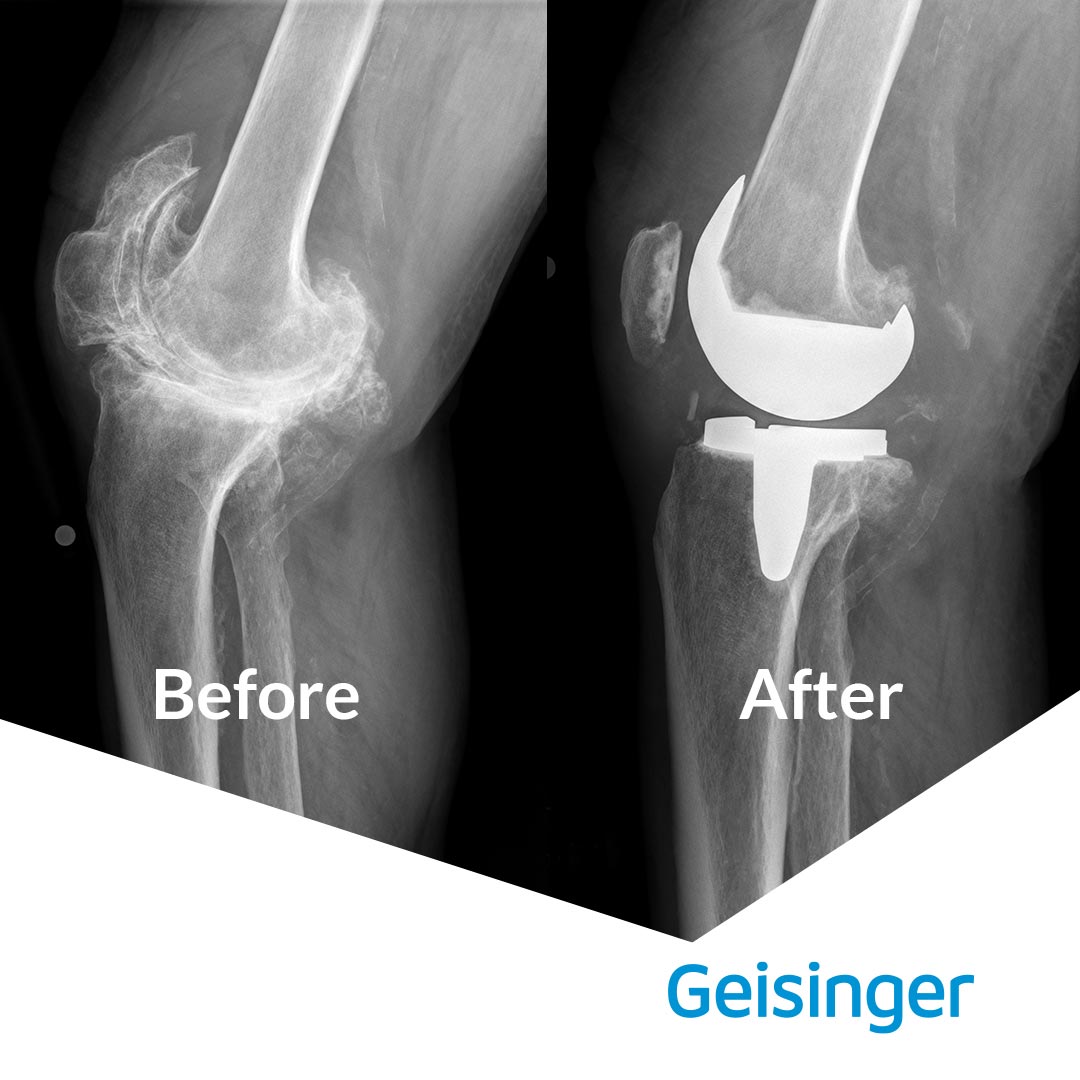

“I had arthritis in both knees. The right knee was especially bad because of an old football injury,” Mr. Cooper explains. “There were numerous bone spurs and one was the size of a golf ball. The X-rays were really something — it didn’t even look like a knee.”

Mr. Cooper had his left knee replaced in the summer of 2017 by Dr. John Lynott at Geisinger Wyoming Valley Medical Center in Wilkes-Barre. The operation went well and he recovered quickly, so he made plans for his right knee to be replaced in the fall of 2018.

Dr. Lynott was able to remove three of the four bone spurs in Mr. Cooper’s right knee — the fourth was too close to his femoral artery. “It did the trick though,” says Mr. Cooper. “I can walk on it without a limp and stand on it just fine. And best of all, the pain is gone.”